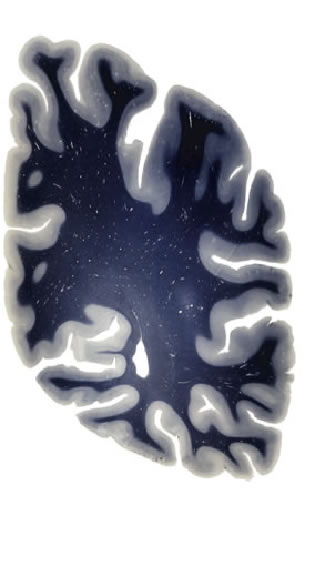

Hi-Resolution Sections · Cells (Nissl Staining) · Virtual Microscopy

Frontal sections (Nissl) from the Atlas Brain:

Macroscopy

Slice ID:

r4-0620

Plate NR:

56

Position:

53,5 mm